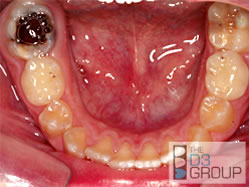

How is Molar Hypomin diagnosed?

Dental professionals will look at the appearance of the affected teeth and the number of affected teeth, as outlined here (WHAT DOES IT LOOK LIKE?). They might also assess sensitivity of the tooth by blowing air or spraying water on it. In many cases, and particularly those made worse by dental decay, "X-rays" (dental radiographs) may be taken to assess the extent of damage.

Why do Hypomin teeth hurt?

In many cases, Hypomin teeth are soft and porous (chalky) and may even start to crumble away during chewing and cleaning (i.e. "break down"). As a result, the sensitive part of the tooth (dentine) may become exposed and react painfully with things such as cold air, hot foods and drinks, or even just toothbrushing. Most treatment for Molar Hypomin aims to cover up the defective areas, thereby protecting against pain, further breakdown and decay.

Is Molar Hypomin different from dental caries?

Yes, Molar Hypomin is really very different from dental caries, but it's common for both problems to co-exist in which case "tooth decay" is an appropriate term to use. Conventionally, dental caries happens when normal tooth enamel is attacked by acids, which are produced by sugar-loving bugs in dental plaque. This acid-attack, which can be aggravated by acidic food and drinks, leads to softening of the enamel and subsequently a cavity may form. Unsurprisingly, in Hypomin teeth (which are already soft and porous), the acid-attack can progress extremely rapidly. In contrast to decay, which only affects teeth that have erupted into the mouth, Hypomin first happens when the tooth is developing within the child's jaw – its cause has nothing to do with sugar and plaque. Once erupted, Hypomin teeth may start to crumble even without

excess sugars or acids in the diet. It's particularly important that Hypomin

teeth are looked after carefully to avoid problems with decay.